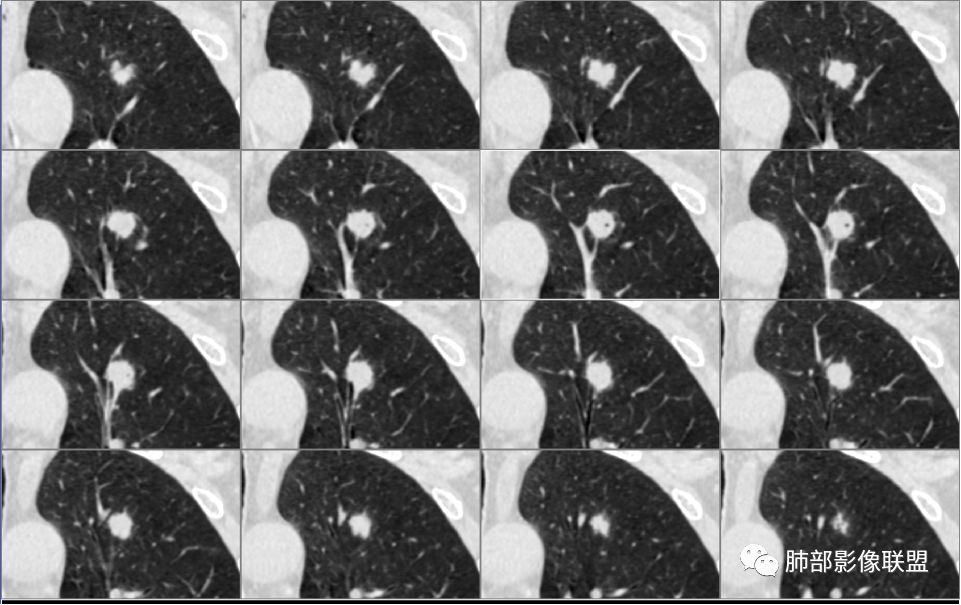

病例1为胸膜下实性小结节,血管脐凹样出入,可见支气管阻塞。病灶膨隆,部分边缘平直,周围晕征不明显,未见分叶,但可见毛刺及胸膜牵拉,增强后明显强化,老年男性,怀疑新生物尤其是腺癌是有理由的。

胸膜下结节,边界清楚、光滑,边缘稍凹陷,有胸膜牵拉

似有浅分叶

门口支气管堵塞——提示与支气管相关,不支持良性肿瘤

除了胸膜牵拉,还有短毛刺?血管纠集

支气管在门口堵塞

综合起来看,恶性不能排除。建议穿刺活检,一定要认清楚:我们影像有局限性。